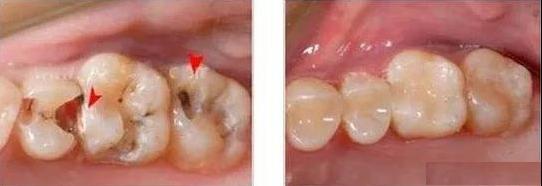

2、大面积龋齿的牙齿,牙齿修复后牙齿本身的抗力往往不足,在咀嚼过程中容易发生冠折。因此,补牙后建议做牙冠保护,防止牙冠断裂。